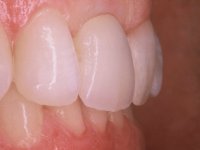

After the impression of the implant using a double-mix technique with double viscosity and the collection of shape and color information by the ceramist, we proceed with the work. In the model, a syn octa was placed over the implant, and a screw was placed on it to assess its emergence in relation to the incisal edge. Then, an adequate emergence profile in the artificial gingiva was prepared. A abutment with characteristics suitable for overbite and simultaneously capable of receiving a veneer was waxed on top of this scenario. This waxing gave rise to the manual milling of a very personalized abutment. An infrastructure in Zr was also made for the veneer with a very great adaptation to the abutment. On this infrastructure ceramics were placed. Ceramic fluorescence sought to compensate for the lack of fluorescence that Zr had and obviously further customize the aesthetics. The adhesive bridge was removed and the definitive work was placed. The syn octa was initially tightened with 35 N to the implant and then the Zr abutment was tightened over the syn octa with 15 N. The access hole was plugged and then the veneer was cemented with resin-reinforced glass ionomer. After 15 years, the patient returned to the consultation with tooth mobility. Fortunately, nowadays we have the possibility of having dynamic tightening wrenches that allow tightening screws with greater inclinations. An access cavity was made without damaging the incisal edge of the veneer. Tightening was done with a dynamic wrench with 15 N torque. The hole was covered with Teflon and filled with composite resin. This solution allowed the problem to be solved in a simple and economical way.